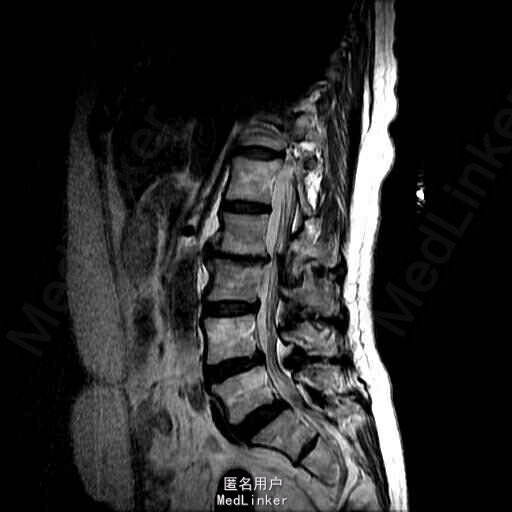

主诉:右下肢麻木伴驼背11年余 病史:患者女性,64岁,11年前无明显诱因出现右下肢疼痛,休息后好转。未予重视,后出现右下肢麻木感,逐渐小狐仙右臀部坚硬,驼背,伴跛行。常感双腿酸胀,腰部疼痛。自行步行距离小于200米,即会发生右下肢僵硬,麻木疼痛。X线检查示腰椎侧弯

查体:脊柱侧弯,上肢无麻木,疼痛感觉异常,腰部右侧疼痛,右下肢及右臀部疼痛,麻木感。双侧肌力及肌张力可,膝腱反射(+),踝反射(+),病理征(—),直腿抬高试验。右侧40度,左侧55度。 辅助检查:腰椎x线片:腰椎侧弯,腰椎退行性改变,L5椎体略行前滑脱 脊柱全长:胸腰段呈S形,L5椎体向前滑脱,L3椎体略变扁,颈胸腰椎退行性改变 MRI:脊柱侧弯,L2-3,L3-L4,L4-L5,L5-S1椎间盘突出,相应节段椎管狭窄

诊断:腰椎侧弯,腰椎椎管狭窄 治疗:手术矫形:早期侧路减压融合,后期再行后路固定。